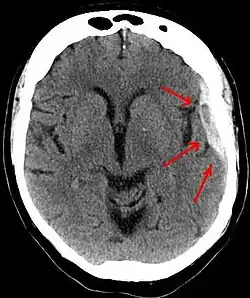

A subdural hematoma demonstrated by CT

A person must receive medical assessment, including a complete neurological examination, after any head trauma. A CT scan or MRI scan will usually detect significant subdural hematomas.

Subdural hematomas occur most often around the tops and sides of the frontal and parietal lobes.[3][2] They also occur in the posterior cranial fossa, and near the falx cerebri and tentorium cerebelli.[3] Unlike epidural hematomas, which cannot expand past the sutures of the skull, subdural hematomas can expand along the inside of the skull, creating a concave shape that follows the curve of the brain, stopping only at dural reflections like the tentorium cerebelli and falx cerebri.

On a CT scan, subdural hematomas are classically crescent-shaped, with a concave surface away from the skull. However, they can have a convex appearance, especially in the early stages of bleeding. This may cause difficulty in distinguishing between subdural and epidural hemorrhages. A more reliable indicator of subdural hemorrhage is its involvement of a larger portion of the cerebral hemisphere. Subdural blood can also be seen as a layering density along the tentorium cerebelli. This can be a chronic, stable process, since the feeding system is low-pressure. In such cases, subtle signs of bleeding—such as effacement of sulci or medial displacement of the junction between gray matter and white matter—may be apparent.